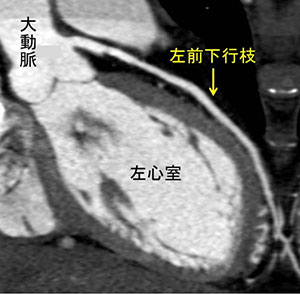

特に、従来、心臓カテーテル検査のみにて描出が可能であった冠動脈を、近年では非侵襲的にCTで評価することができるようになりました(図3)。冠動脈病変は、心筋梗塞症や狭心症の原因となるため、その評価は大変重要です。この他、大動脈瘤などの大動脈疾患や、心臓腫瘍・血栓の有無などの評価もできます。また、CT機器の進歩により、現在は患者さんが受ける被ばく線量の低減や、造影剤投与量の減量も可能となりました。

• 図1:心臓CT水平断画像